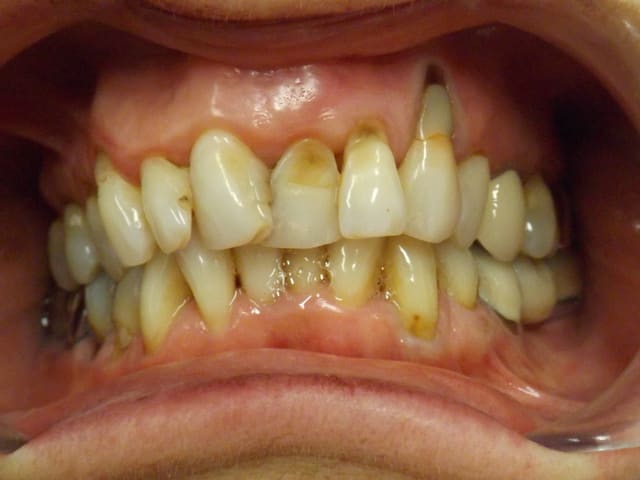

Dame de soixante cinq ans. Motif de consultation esthétique, et elle est préoccupée par la 23.

Quel traitement lui proposeriez-vous pour le bloc incisivo-canin supérieur ?

Pas de mobilité ni de poches paro, pas d'hypersensibilité dentinaire, tests de vitalité positifs, sauf la 23 qui est dévitalisée. Sourire non gingival.

Il me semble que la malposition est telle qu'elle n'est pas rattrapable par des facettes, et peut être faut-il effectivement envisager des CCC, et sans doute que les wax up m'aideront à confirmer ce choix, je vais commencer par ça.

Ici, sans ortho, point de salut. On a un sourire très "animé".

Contente toi du minimum, à mon avis. Vu l'état de la 23, pas besoin de sortir la grosse artillerie, c'est une dent condamnée à moyen terme.

De plus on aperçoit l'état des dents postérieures. Traitement global ?

+1, on aurait besoin d'expansion (pas évident à cette âge), l'occlusion est foireuse, et les antérieures en souffre énormément. Un traitement global est a envisager, peut être qu'avec un beau mock-up tu pourrai motiver ta patiente. Pour la 23 si l'origine de la lésion paro (certainement occlusale) n'est pas réglée, ça va de toute façon finir dans le haricot!

Pour moi pas touche aux antérieures si toute l'occlusion (postérieure et antérieure) n'est pas équilibrée.